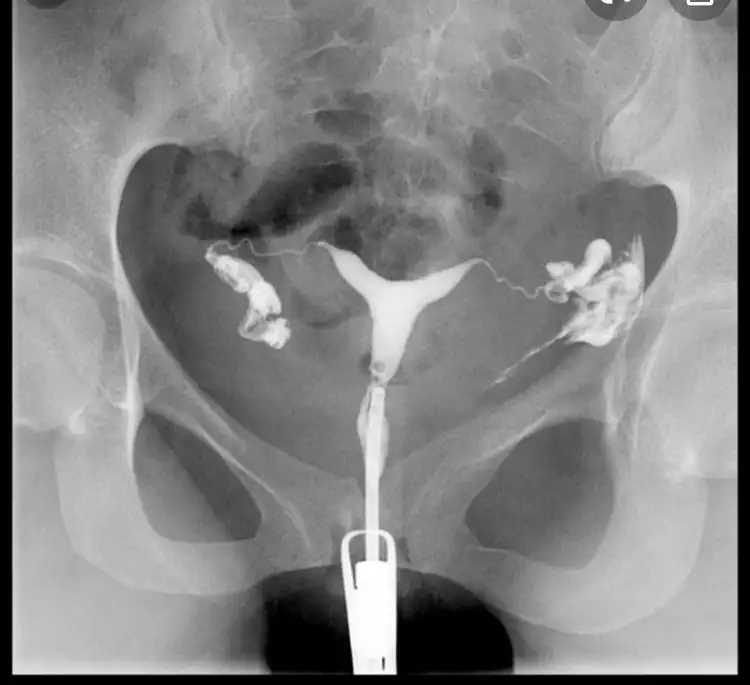

Filmden anlayan varsa bakabilir mi? Bi radyologa sorduk sol normal tüp görüntüsü o boğum boğum olan dedi, sağda da tıkanıklık varmış ama görünüyor opak madde geçmiş dedi. Bi sağlık çalışanına daha sorduk o da opak madde geçmiş yapışıklığı açmış dedi sizce? Turuncu olan az verdiği hali pembe olanlar basınçlı verdiği hali